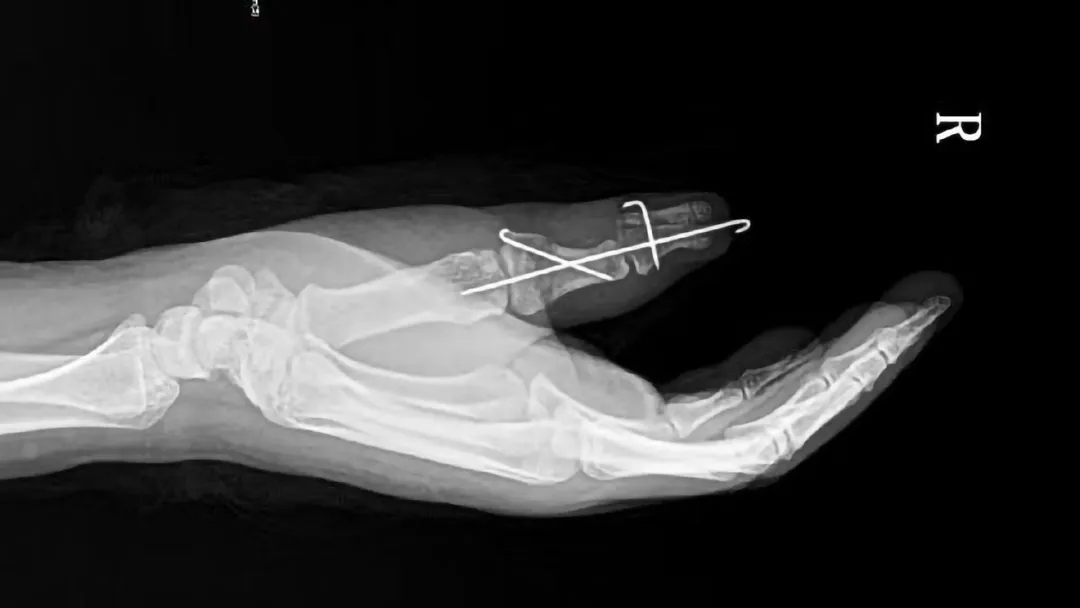

为了达到最佳治疗效果,还小奕一个美好未来,重庆红楼医院骨科主任汪主任组织全科室进行手术方案讨论,汪主任告诉我们,患者拇指多指畸形对手部功能影响大,为求满意的效果,需将右拇指多指切除、矫形后原位再植、近节指骨截骨矫形、指间关节囊、肌腱修复、局部转移皮瓣修复、指间关节脱位复位内固定等多个手术复合进行。

(术后)

重庆红楼医院汪主任专家团队,凭借精湛的医术,历时5小时,完成了复杂的修复手术,成功将患者畸形的拇指重塑成形。蟹钳手不见了,小奕的微笑回来了,小奕母亲的自责也少了,在他们肩上,曾经压得他们喘不过气来的思想包袱,已经卸下。小奕的母亲激动地告诉我们:“这几年,很少看到她笑过,这段时间,她笑的次数很多,我心里也很开心,手好了,她的未来也就好了,真的很感谢你们医生!”